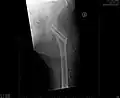

- Zugschraubenosteosynthese bei einer medialen Fraktur. Behandlung einer nicht dislozierten medialen Schenkelhalsfraktur bei einer 92-jährigen Patientin.

-

Aufnahme vor der OP. a.p.-Aufnahme. Die Fraktur ist mit einem Pfeil markiert. -

Seitliche Aufnahme. Die Fraktur ist mit einem Pfeil markiert. -

Nach OP mit Zugschrauben, a.p.-Aufnahme. Man sieht die noch liegende Redondrainage. -

Seitliche Aufnahme.